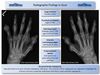

hand

A

other hands

A

PA, OA